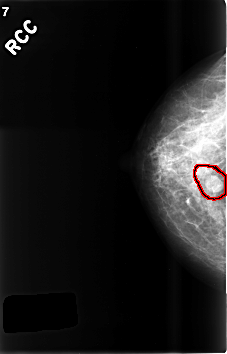

FILE: C_0507_1.RIGHT_CC.OVERLAY

TOTAL_ABNORMALITIES 1

ABNORMALITY 1

LESION_TYPE MASS SHAPE OVAL MARGINS CIRCUMSCRIBED

ASSESSMENT 3

SUBTLETY 5

PATHOLOGY BENIGN

TOTAL_OUTLINES 2

BOUNDARY